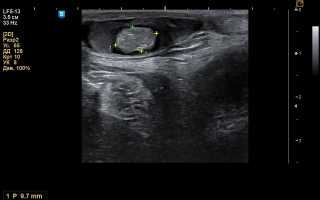

Дермоидная киста на УЗИ

Данный вид обследования позволяет точно оценить состояние пораженного органа, дает точную информацию о формировании новообразования. Ультразвуковое обследование позволяет выявить локализацию дермоида, определить объем, содержимое капсулы, влияние новообразования на соседние органы. Дермоидная киста надбровной дуги, как и дермоиды, локализованные в других областях, определяются в масштабах реального времени (3Д, 4Д проекции). УЗИ является необходимым методом исследования для дифференциации дермоидной кисты промежности и мезенхимомы.

Вышеперечисленные симптомы заставляют обратиться женщину к врачу, который проводит осмотр и назначает ряд исследований. В перечень входит и УЗИ органов малого таза с допплерографией (метод исследования кровотока в сосудах с помощью ультразвука). Метод информативен в отношении дифференциальной диагностики между доброкачественным и злокачественным новообразованием.